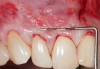

Fig 9. Two years postoperative. A complete root coverage and increase of the zone of attached and keratinized tissue is observed.

Figure 9

Fig 10. Cross-sectional view of the preoperative and postoperative (2 years). A three-dimensional increase of zone of keratinized and attached tissue is observed, restoring the lost attachment apparatus and correcting the gingival deformity in height and width.

Figure 10

Fig 11. Cross-sectional view of the preoperative and postoperative (2 years). A three-dimensional increase of zone of keratinized and attached tissue is observed, restoring the lost attachment apparatus and correcting the gingival deformity in height and width.

FIgure 11